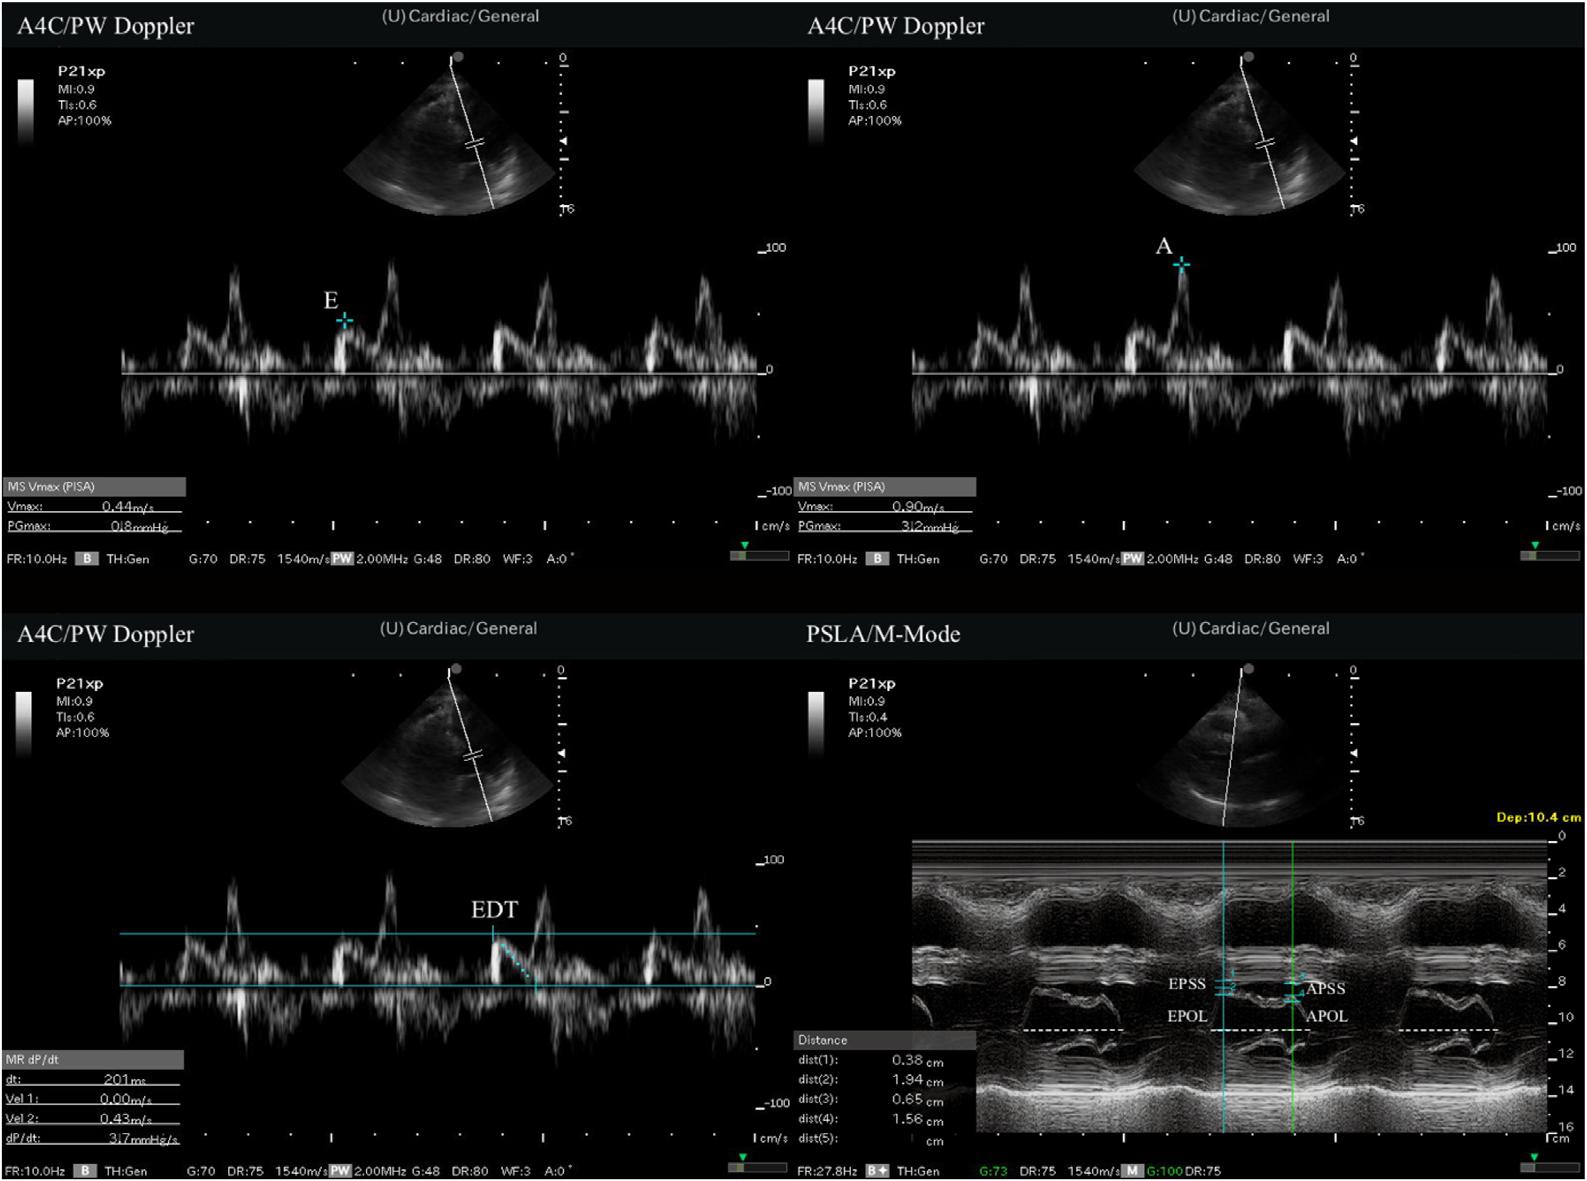

DopplerinA4Cview.ThenEPSS,A-pointseptalseparation (APSS),A-pointopeninglength(APOL),andE-point openinglength(EPOL)weremeasuredwithM-mode evaluationatthelevelofthemitralvalveinthePSLAview. Theejectionfraction(EF)wascalculatedusingtheEPSS method.MeasurementtimewasrecordedforbothA4Cview measurementsandPSLAviewmeasurements.Therecording procedurecommencedoncetheultrasonographicwindows providedbytheimageswereclearlyvisible,anditwas concludedwhenthedesiredmeasurementshad finished.All measurementsaresummarizedin Figures2 and 3

Figure2. Illustrationofmeasurements. PSLA,parasternallongaxis; A4C,apicalfour-chamber; PW,pulsedwave.

Figure3. Measurementsofpoint-of-careultrasound. A,latediastolevelocityofthemitralinflow; A4C,apical4-chamber; APOL,A-pointopeninglength; APSS,A-pointseptalseparation; E,early diastolevelocityofthemitralinflow; EDT,Edecelerationtime; EPOL,E-pointopeninglength; EPSS,E-pointseptalseparation; PSLA, parasternallongaxis; PW,pulsedwave.